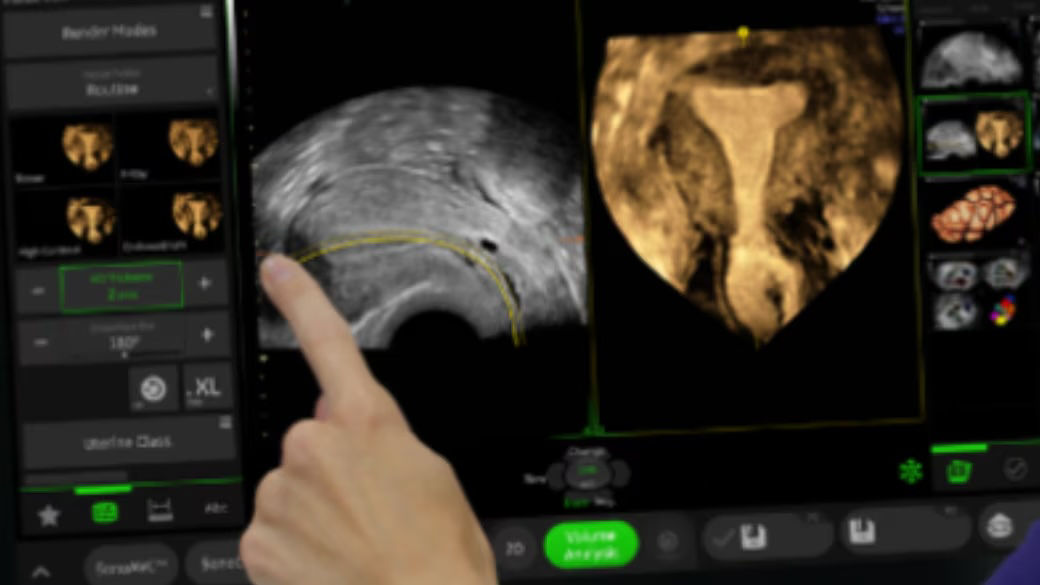

Next level color Doppler for easy, fast visualization of blood flow, displaying a 3D-like appearance.

Uses Color Doppler amplitude to create a 3D-like appearance, helping to clearly separate blood vessels with less flash artifact, improving vessel edge clarity. Available in all color modes, Radiantflow can also be combined with other imaging techniques like spectral Doppler and color M-mode, making it especially useful for visualizing major vessels such as the 3-vessel view (3VV), umbilical cord, arotic arch, and more.